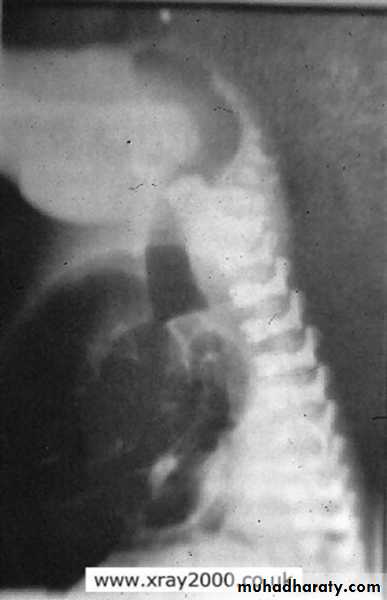

congenital megacolon (Hirschprung disease )

• There is one or more segment of colon devoided from innervation resulting in constriction with proximal dilatation of rest of colon due to weak innervation .• The agangloinic segment usually short , at or near the recto- sigmoid junction .

congenital mega colon

• Rarely the whole colon can be affected result in micro-colon .• 5. Clinically the patient suffering from constipation and abdominal distention since birth .

• 6. The value of Ba Enema is to spot the narrow segment especially prior to surgery .

• 7. Instant Ba Enema is usually done and the Barium used is usually hypertonic .

• Views of particular importance include:

• early filling views that include rectum and sigmoid colon allowing for rectosigmoid ratio to be determined.

• transition zone